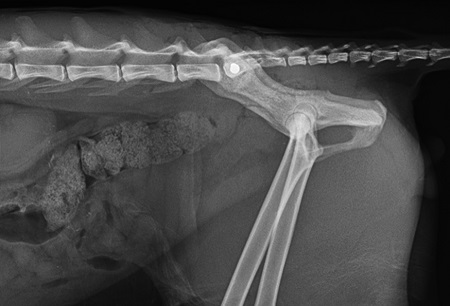

Abbildung 3

Die Lastübertragung in der Bewegung erfolgt von den Hinterbeinen über das Hüftgelenk auf die Darmbeinsäule. Von hier wird die Kraft über das Iliosakralgelenk auf die Wirbelsäule übertragen. Alle Frakturen/Luxationen, die sich im Bereich dieser Linie befinden, bedürfen einer chirurgischen Stabilisierung. Am Beispiel dieses Patienten ist somit die Iliosakralgelenkluxation rechts versorgungsbedürftig. Die Ischiumfraktur befindet sich nicht im lasttragenden Anteil des Beckens und kann konservativ behandelt werden. Die Einengung des Beckenkanals wird allein durch die Reposition des Iliosakralgelenks korrigiert.

Das Ziel der chirurgischen Stabilisierung ist die Wiederherstellung des physiologischen Beckenrings und die Sicherstellung einer frühzeitigen Lastaufnahme.